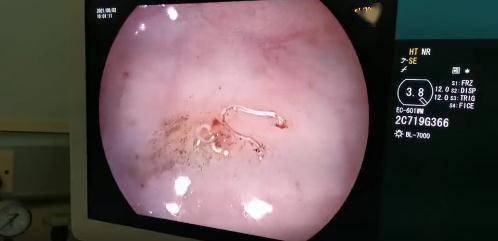

7月初 , 小青因头晕、乏力、浮肿又来到中山市博爱医院肾内科就诊 。 医生对小青做了过敏原测试、免疫化验、大便找虫卵等检查 ,结果都是阴性 , 最后又进行了胃肠镜检查 。 主治医师尹泉一看 , 吓了一跳 , 肠腔内布满了活生生蠕动的小虫子 , 真正的“元凶”水落石出 。

请谨慎点击图片↓↓

文章图片